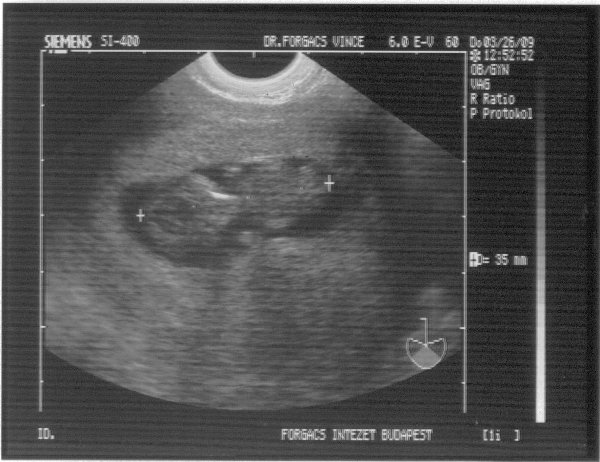

És ezt írta a doki:

"A terhes méh üregében egy szabályos petezsák látható. Átmérője 52 mm. Benne egy élő embryo. CRL: 35 mm. Ritmusos szívműködés, négy végtag és intenzív embryonális mozgás látható. A korábban látott többi petezsák közül már csak egy kicsiny 12 mm-es látszik, benne embryonális elem nem látható. A méh környezetében kóros képlet nincs.

A látott kép AIH révén fogant, élő, intact, 10 hetes singularis intrauterin terhességnek felel meg."